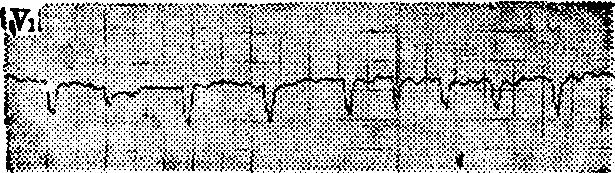

图1 心房扑动2:1心电图

图2 心房颤动心电图

心房扑动: 无P波,以F波代之,频率每分钟250~350次、间距均匀、波形一致并连续成锯齿状,无等电位线;QRS波群呈室上型; 由于不同比例的房室传导,心室率往往较心房率慢,节律规则或不规则。如F波的间距与形状略有差异,且频率每分钟>300次者,称不纯性房扑或心房扑动颤动。

心房颤动: 无P波,以一系列大小、形态及间距不一的f波代之,频率为每分钟350~600次;QRS波群为室上型,形态略异,心室律完全不规则。